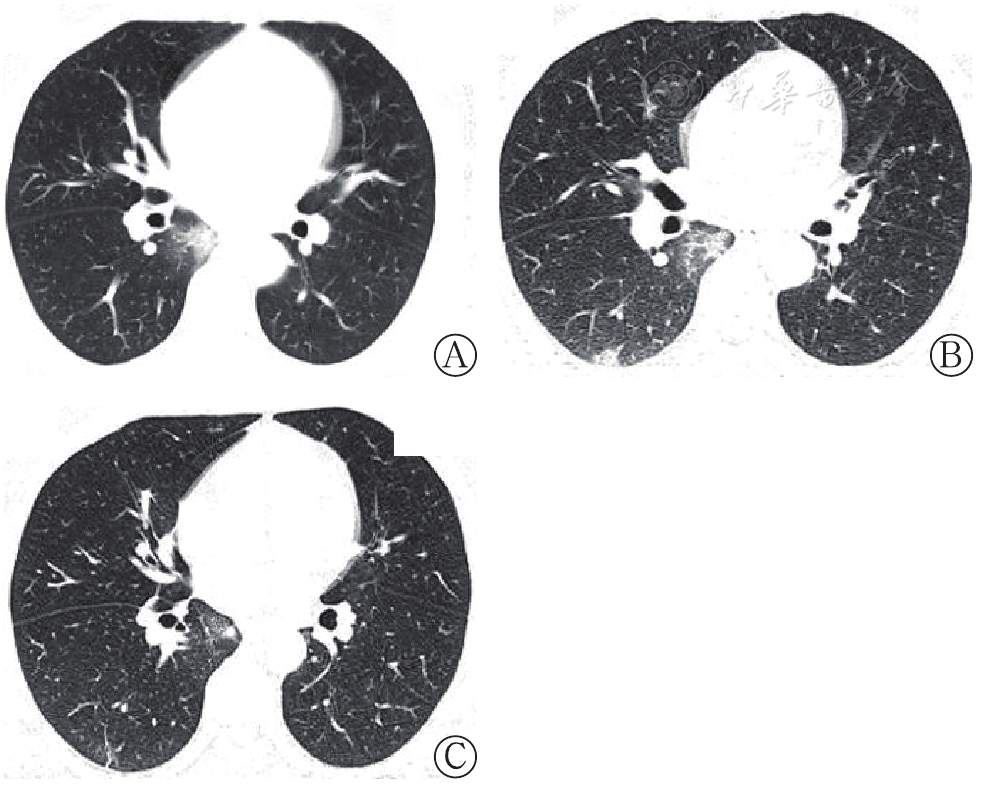

研究纳入病例中26例(81.25%)接受了胸部X线计算机断层摄影术(CT)检查。1例41岁男性新型冠状病毒肺炎确诊病例,入院CT结果提示:右肺下叶后基底段胸膜下磨玻璃样结节与实变混合病灶(图1A);6 d后复查提示病灶进展,表现为面积增大且部位增多(图1B);经积极的支持治疗和抗病毒治疗,13 d后复查CT提示病灶基本吸收,残留少许条索灶(图1C)。其余病例均提示较为典型的新型冠状病毒肺炎影像学表现[5]:两肺多发斑片状磨玻璃阴影、实变影,多沿支气管血管束和胸膜下分布为主,其间可见增粗的血管影,表现为细网格状影,呈"铺路石征" 。也可以表现为极为淡薄的磨玻璃阴影,小血管周围有局限性磨玻璃阴影。